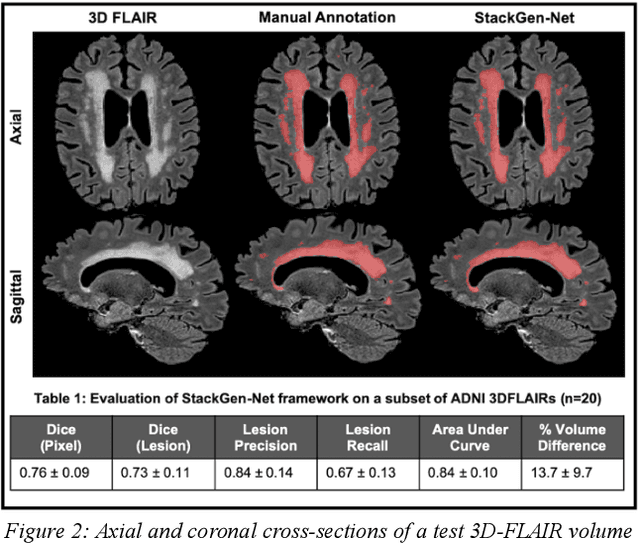

Abstract:The relationship between cognition and white matter hyperintensities (WMH) volumes often depends on the accuracy of the lesion segmentation algorithm used. As such, accurate detection and quantification of WMH is of great interest. Here, we use a deep learning-based WMH segmentation algorithm, StackGen-Net, to detect and quantify WMH on 3D FLAIR volumes from ADNI. We used a subset of subjects (n=20) and obtained manual WMH segmentations by an experienced neuro-radiologist to demonstrate the accuracy of our algorithm. On a larger cohort of subjects (n=290), we observed that larger WMH volumes correlated with worse performance on executive function (P=.004), memory (P=.01), and language (P=.005).